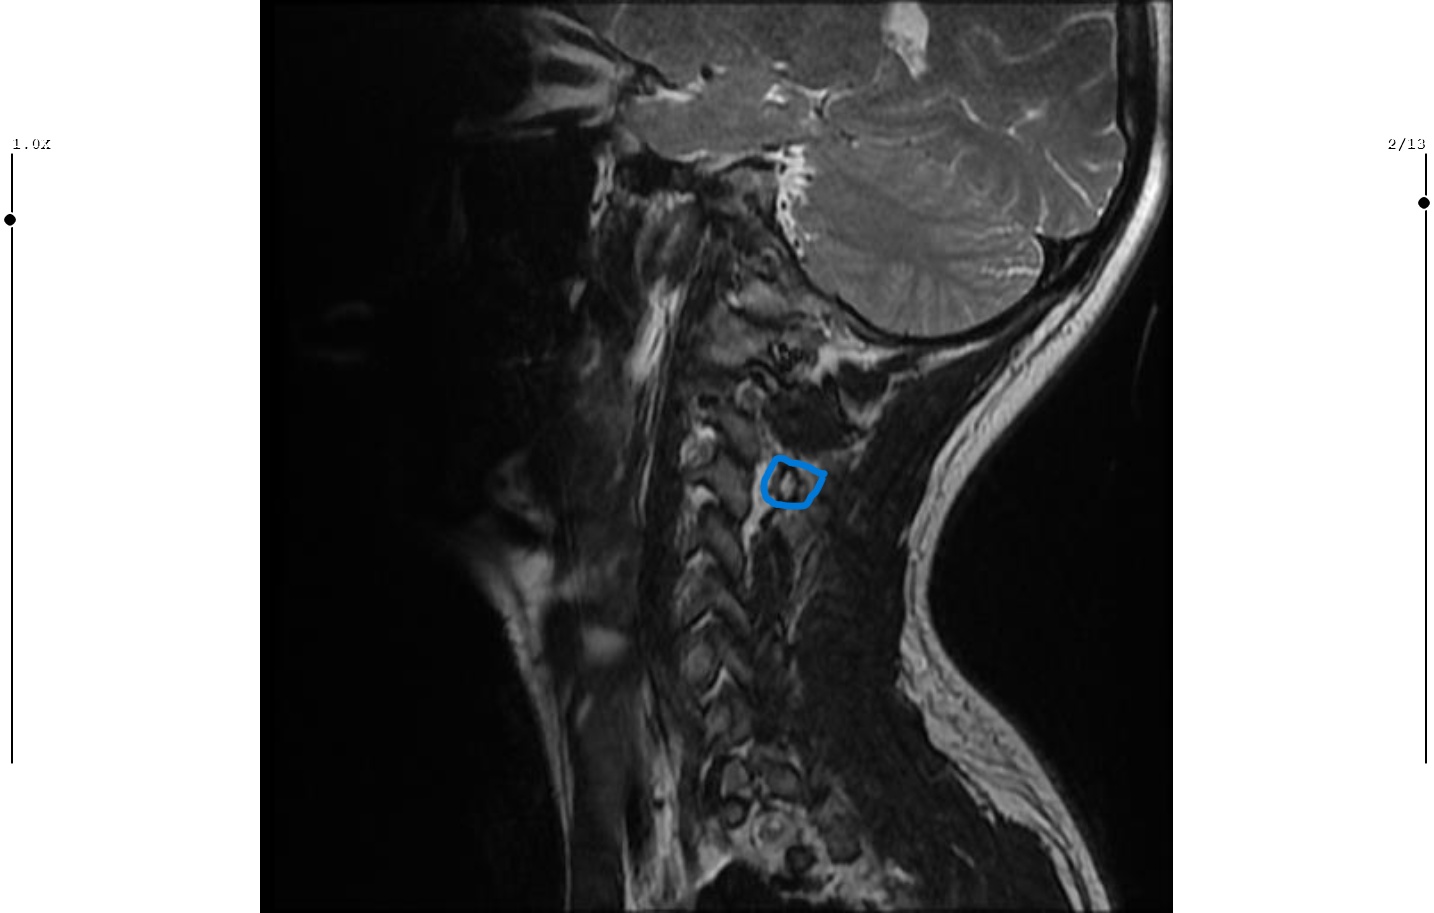

Boyun düzleşmesi ve boyun fıtığı başlangıcı var

• c5c6c6c7 fıtık.png

c5c6c6c7 fıtık.png

• boyun arkası c5c6c6c7 fıtık.png

boyun arkası c5c6c6c7 fıtık.png